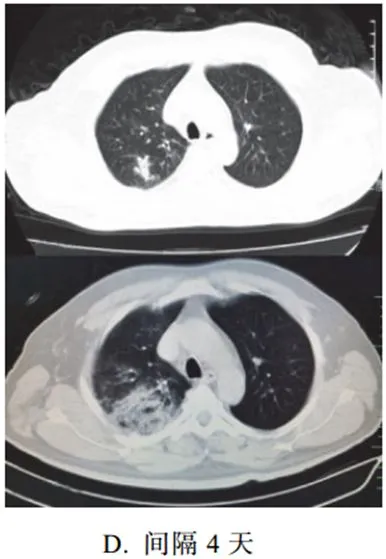

三、重症期征象

新冠肺炎肺部病变一般在发病后 14 天左右达到高峰,少部分病例急剧进展,病变累及双侧全肺,呈白肺征象,其内可见空气支气管征,双侧胸腔可有少量胸腔积液,临床纳入危重症管理

根据既往病理学机制提示肺泡腔有大量纤维素性渗出

3. 重症期表现为大范围肺组织密度增高实变,少数呈白肺征象